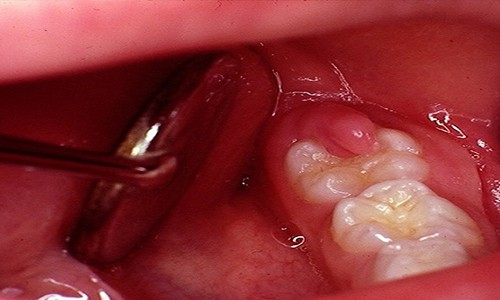

CASO CLÍNICO 1

Pacente con presencia de tercer molar en proceso de erupcion dental, (pericoronitis)